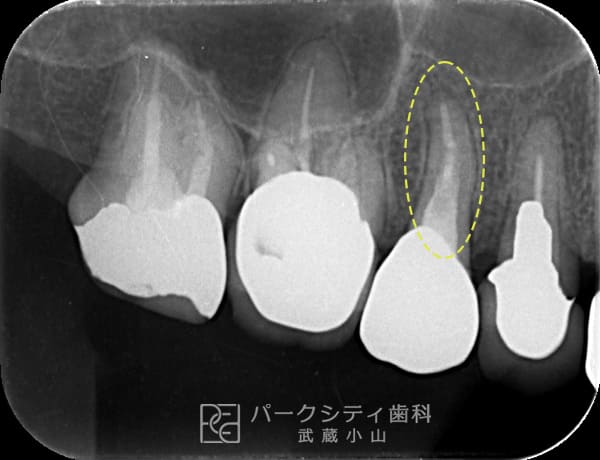

術後

1年経過

- 主訴

- 歯茎がたまに腫れる

- 治療法

- 根管治療

- 治療期間

- 1か月

- 費用

- 保険治療

慢性根尖性歯周炎の症例です。根管治療をして改善しました。1年経過後も予後が良好です。